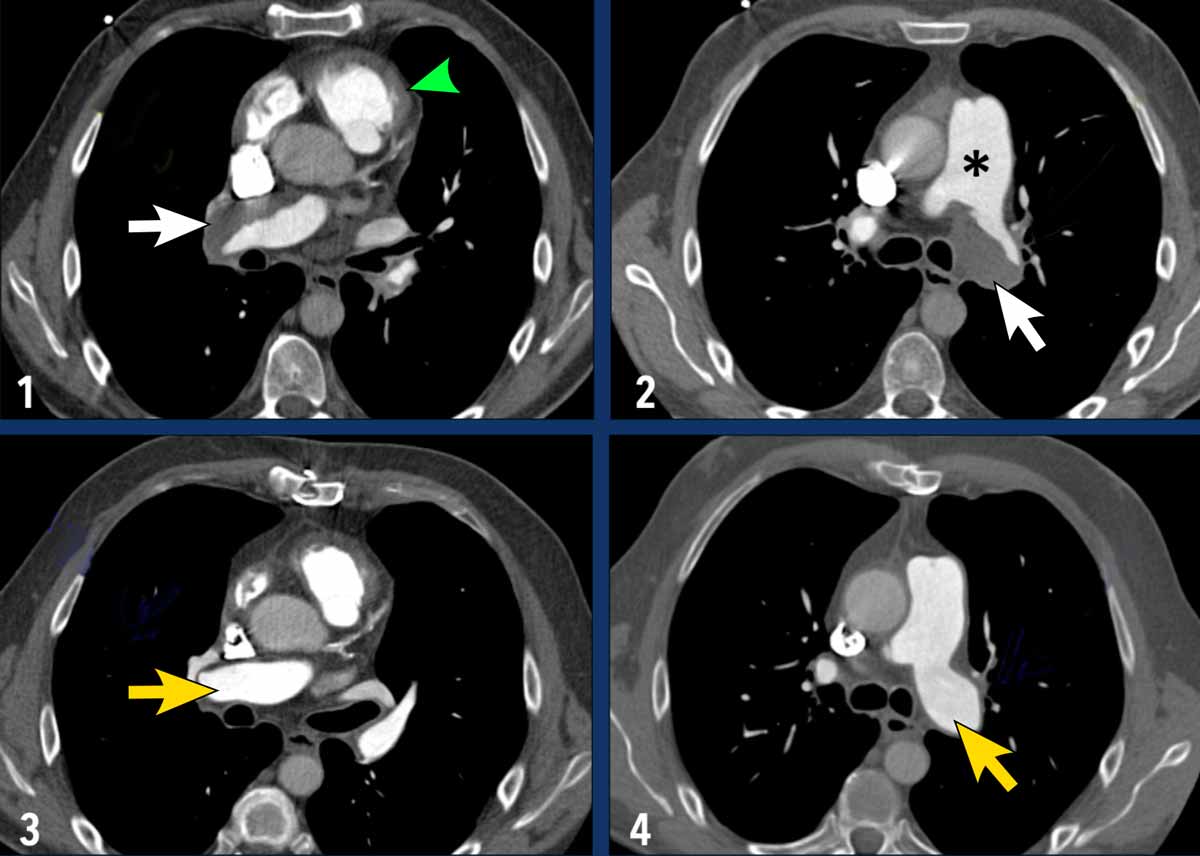

Imaging

• Pre-endarterectomy (Images 1-2): wall adhering thrombotic material is seen in both the right and left pulmonary arteries (indicated by white arrows). Notable dilatation of the main pulmonary artery (asterix) and hypertrophy of the wall of the right ventricular outflow tract (green arrowhead) is also present.

• Post-endarterectomy (Images 3-4): The pulmonary arteries on both sides are cleared of thrombotic material.

Images

• There is a large filling defect within the central pulmonary arteries.

• Notably, there is no distinct right ventricular hypertrophy or dilatation.

• Progressive size despite anticoagulation therapy.

• Metabolic activity on FDG-PET imaging.